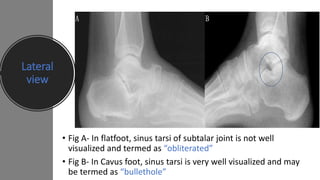

Lateral

view

• Fig A- In flatfoot, sinus tarsi of subtalar joint is not well

visualized and termed as “obliterated”

• Fig B- In Cavus foot, sinus tarsi is very well visualized and may

be termed as “bullethole”